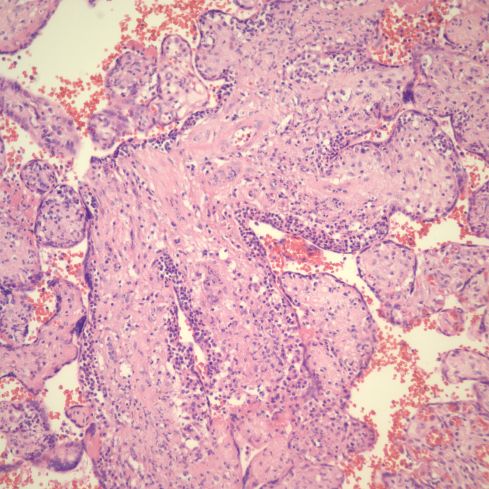

Fig 28) There is core of villi enmeshed in a basophilic matrix surrounded by villi demonstrating VUE. The rectangle is shown at higher magnification in the next figure. (H&E, 4X)

Fig 29) At higher magnification, the basophilic matrix can be seen to be similar to the fibrinous fibrinoid matrix of perivillous fibrinoid deposition with the addition of numerous inflammatory nuclei from perivillus and subsyncytial inflammatory cells. (H&E, 20x)

Fig 30) Another similar focus of enmeshed villi with VUE in another area of the same placenta as figure 5609. (H&E, 4x)